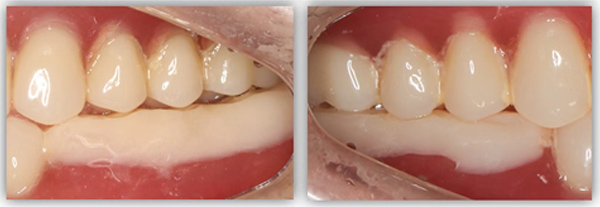

单颗是最常规的种植,不能因为常规就觉得简单,治疗时要追求小而精。从适应证把握到术式选择,再到修复方式,术后的结果有没有达到术前预期效果,都需要用心设计,事后复盘。这位患者是一位来自外地的年轻老师,有一颗6号牙需要种植。她只有在暑假两个月的时间内可以来院,希望能在暑假期间完成治疗。

为满足患者的需求,我为她制订了一个即拔即种、种植后早期负重的方案,把五个治疗步骤缩减为三步。首次来院时,我为她完成了拔牙、种牙和安装基台,6周后来院拆线和取模,两周后完成牙冠修复,也就是戴牙。整个治疗周期仅8周,不到两个月就完成了。

6号牙也就是第一磨牙,是最早萌出的恒牙,比较容易龋坏。它虽然不在前牙美学区,不太容易影响容貌,但出于对美学的高要求,我在设计方案时也考虑了是按常规流程先拔牙,再备洞,还是以修复为导向,先按现有的牙冠来确定未来修复体的形状,再去反推种植体植入的位置。后者对医生来说难度更高一些,但更有利于复原天然牙的形态。

为保证这个方案的顺利实施,我通过查阅文献去印证方案的可行性,还为她建议了适合的种植体,原来三个月的骨结合时间能缩短为两个月,种植体功不可没。

这位患者不到60岁,但由于后牙全部缺失多年,残留的前牙已松动且上下无法接触,他基本没办法正常咀嚼,人非常消瘦。完成治疗后我跟踪了这个病例一年,从前后对比照片可以看出,能正常吃东西后他的脸上渐渐也有肉了。